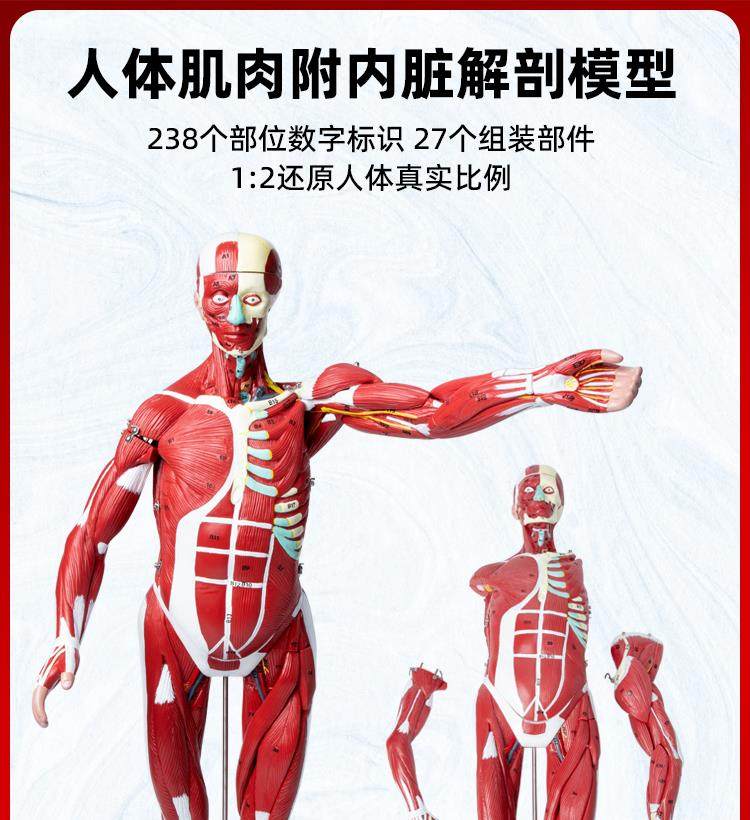

Human Body Muscle Internal Organ Disassembly Anatomy Structure Model Tissue Exercise Artificial Medical Teaching Aids

- Brand: Jianuo Medical

| Model | 6622 |

| Color Classification | 85 Human Muscle Internal Organs Removable Organ,50cm Muscle Model |